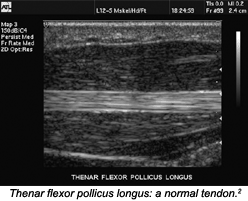

Sonographically, tendons appear as fibrillar structures with hypoechoic (resulting in a bright tissue appearance) collagen fibers and hyperechoic (resulting in a dark tissue appearance) endotendineal septa intermingled between them. The number of fibrils visible with sonography correlates closely with the frequency of the ultrasound probe used. With MRI, normal tendons appear as homogenous hypoechoic structures; therefore, ultrasound can be used to evaluate the tendon in a more dynamic manner, once the location of an injury has been identified.